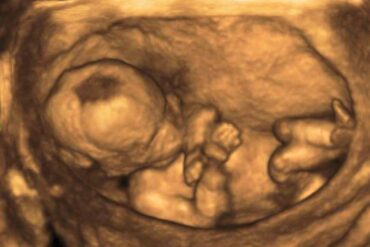

Policie zatím nenašla ženy, které zdravotníci v pondělí zaměnili v pražské Fakultní nemocnici Bulovka a jedna z nich kvůli tomu potratila. Policie dnes na...